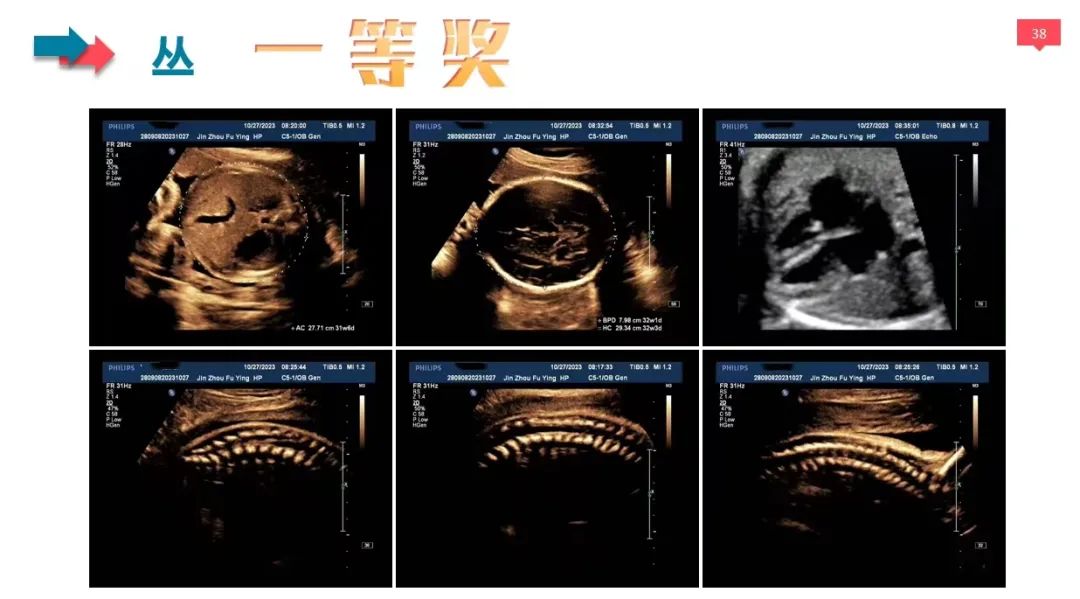

本次大赛共有26名医生参赛,分为I级检查、II级检查、III级检查和NT检查共4个组别,参赛医生上交3~15张图片不等,为了保证比赛的公平公正,评选采取盲评的方式,医生提交参赛作品时不使用真实姓名,而是被赋予毛主席的《卜算子·咏梅》中的一个字作为编号。

经过5位评委的独立评审和2位主任的审核,每组评选出6个作品进入更为严格的第二轮评选,第二轮评选由全体评委及审核共同对入围作品的得分点及扣分点进行逐一商确,最终每个组别分别评选出一等奖1名,二等奖2名,三等奖3名。